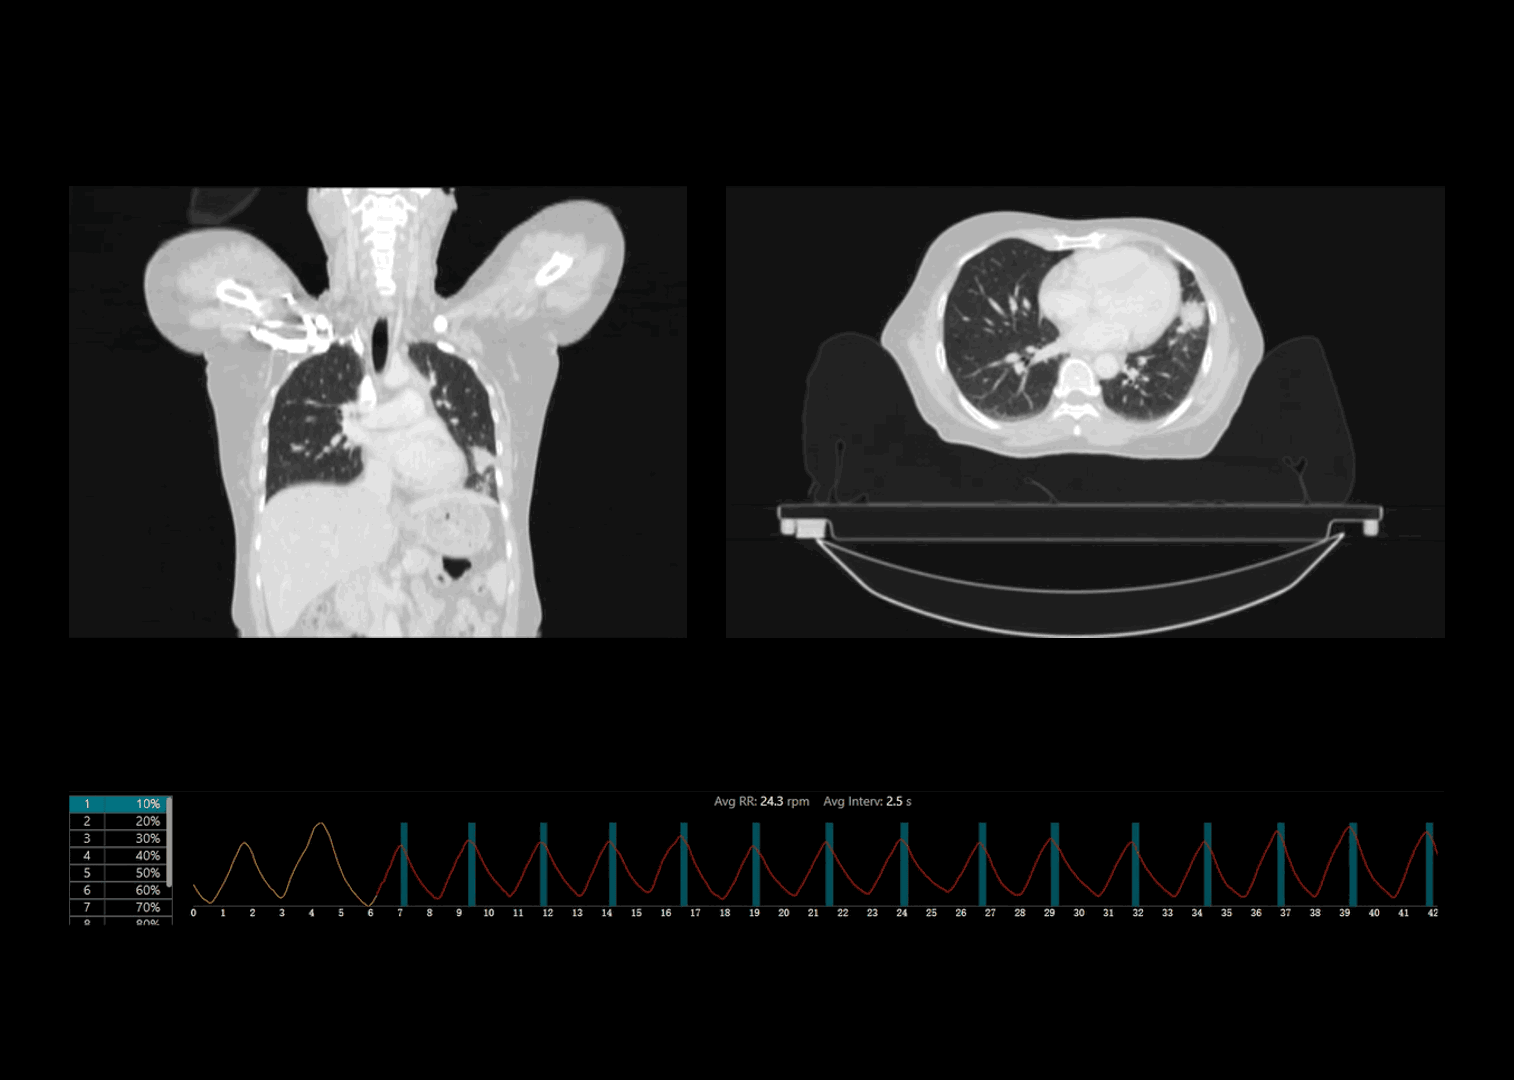

呼吸信号精准探测

联影自研压力传感式呼吸门控系统精准记录规律呼吸、咳嗽异常等各类临床场景下的呼吸信号

自适应螺距采集

基于实际呼吸频率情况自适应推荐最佳螺距参数,相较于传统固定螺距采集,有效减少图像运动伪影

肺部病灶4DCT高清成像